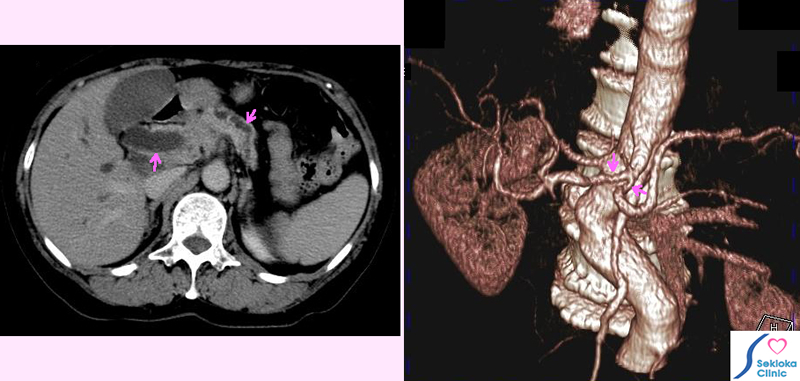

膵臓がんCT

超音波エコーで胆管、膵管の拡張と膵臓頭部の腫大認め、膵臓がん疑い

造影CT検査施行。腹腔動脈などへのがんの浸潤認めました。

血管への浸潤が既にあるため、手術による摘出は困難と判断され、黄疸治療

のため総胆管へのステント挿入。化学療法後、保存的治療。